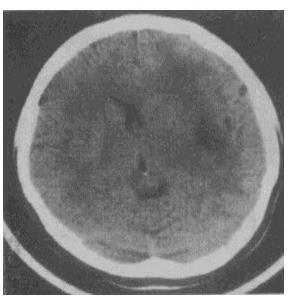

- 单项选择题 女性,48岁。渐进性右侧肢体活动不灵2个月,无发热。既往无任何病史。CT检查见图,应首先考虑以下哪种疾病()。

- C